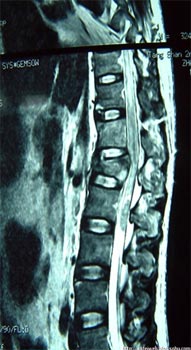

下图是脊髓损伤的照片,脊髓受压变性。